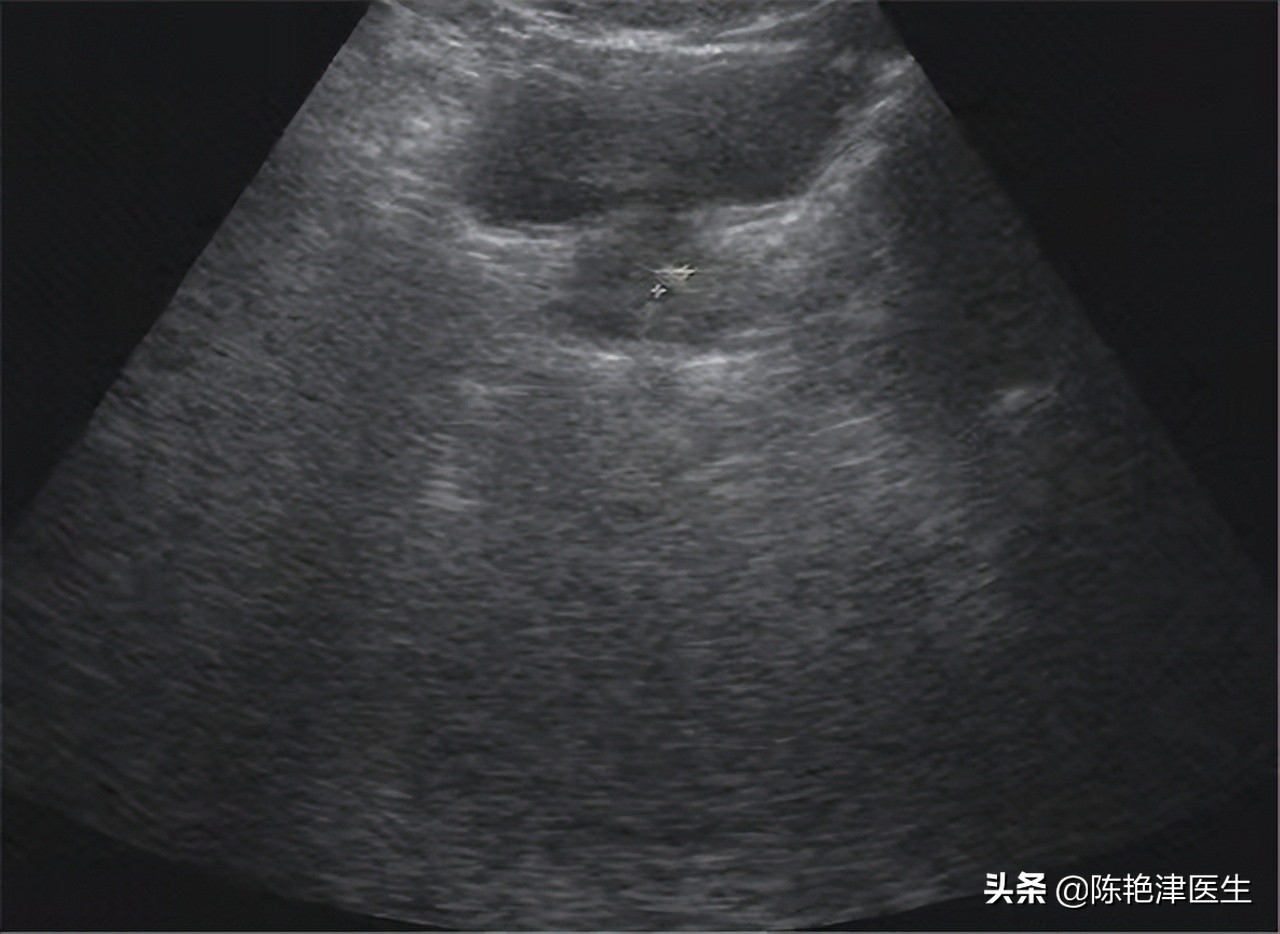

一般的体检项目中都含有B超,B超能够简单筛查一些疾病, 彩超比B超的分辨率更高一些 ,因此一些体检机构会用彩超来筛查肿瘤。彩超和B超都属于超声检查,B超是二维超声检查,彩超是三维和四维超声检查,B超是黑白灰三色,彩超的颜色更丰富,更便于我们观察。

但是本质上两者没有太大区别, 我们平常体检中的B超就能筛查出一些疾病,没有必要专门彩超 ,当然彩超检查还是能够有效防止B超漏诊的情况发生的,必要时我们需要进行彩超检查。

超声检查是最常用的检查手段,相比B超,彩超的准确度会高一些,因此许多疾病确诊都离不开超声检查,超声检查对确诊晚期前列腺癌非常重要,正是因为这一作用,许多体检机构会宣称前列腺彩超能够筛查前列腺癌。

从这三种分类可以大致了解到前列腺癌的进程特点,早期症状表现较轻,肿瘤物质易隐藏。彩超检查的主要作用是利用多普勒原理观察机体内的血流情况和脏器形态,通过前列腺彩超检查是筛查不出早期前列腺癌的,当前列腺发展到晚期时,简单的B超检查都可确诊,B超比彩超的价格更实惠。

另外,我们做腹部超声检查时都要求憋尿,憋尿的意义就是在于便于观察组织间的区别,憋尿能够使膀胱更立体,提高组织对比度,从这一点可以看出彩超来观察组织病变的准确度较低。

总体来说, 前列腺彩超筛查前列腺癌是白费功夫,没有必要;有筛查前列腺癌需求的人群可以做前列腺特异性抗原检测试,对早期前列腺癌筛查的准确度很高。